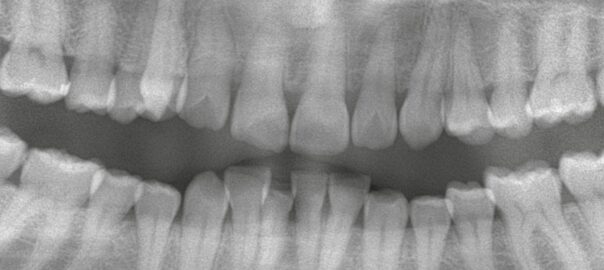

- 2026/01/30 ブリッジが外れる・痛い…インプラントへ変更した症例

こんにちは、静岡市駿河区石田の小嶋デンタルクリニックです。 これまで欠損部にブリッジ治療を行っていたものの、 ・ブリッジが外れる ・噛むと痛みが出る といった症状を繰り返すため、ご相談に来院された患者様です。 ブリッジ治 … 続きを読む ブリッジが外れる・痛い…インプラントへ変更した症例